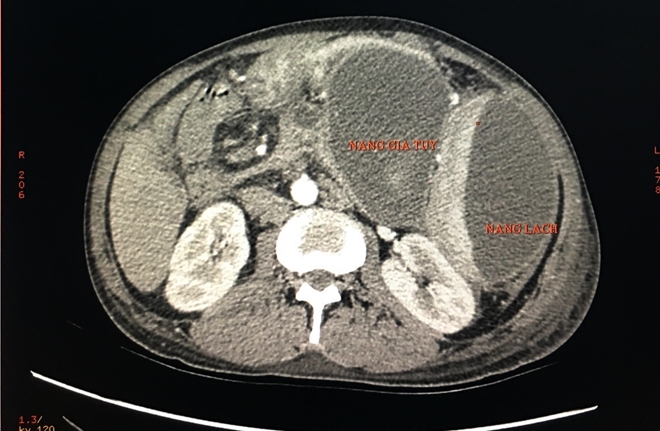

| Hình chụp lại từ hình ảnh CT bệnh nhân. |

Nang giả tụy là một biến chứng muộn của viêm tụy cấp, viêm tụy mạn và chấn thương tụy. Thể hiện bằng sự tụ dịch bất thường ở vùng quanh tụy với một vách được tạo bởi mô xơ viêm mạn. Trước đây, phẫu thuật bóc tách nang hay mở thông nang ruột là phương pháp chủ yếu để điều trị. Tuy nhiên điều trị phẫu thuật, bệnh nhân phải chịu một cuộc phẫu thuật lớn, tỷ lệ tử vong và biến chứng còn tương đối cao.

Hiện nay dẫn lưu nang giả tụy bằng stent đặt xuyên thành dạ dày và tá tràng qua nội soi được xem như một thủ thuật hiệu quả và an toàn hơn. Đây là trường hợp đầu tại ĐBSCL sử dụng phương pháp nội soi tiêu hóa can thiệp thành công trong điều trị nang giả tụy.